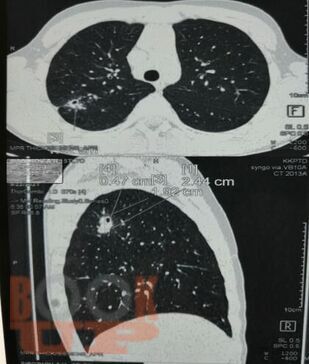

Учебное пособие составлено в соответствии с требованиями ФГОС ВО по специальностям 31.05.01 Лечебное дело и 31.05.02 Педиатрия, рабочей программы дисциплины «Фтизиатрия». В пособии представлена клиническая классификация туберкулеза, но сделан акцент на локализацию туберкулеза органов дыхания, иллюстрированная рентгенологическими снимками больных, лечившихся в КГБУЗ «Красноярском краевом противотуберкулезном

диспансере №1» с 1980-х г. по настоящее время, также даны определения различным формам туберкулеза органов дыхания.